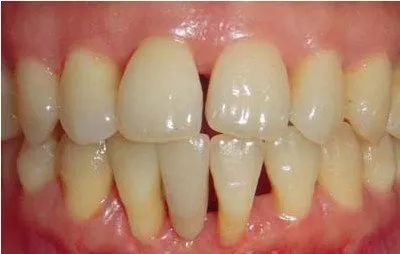

“牙龈线下移”,即牙龈萎缩,指的是牙根部位的牙龈退缩,将牙根暴露出来。牙龈萎缩不可小觑,如不重视,严重者会出现牙齿松动,甚至脱落。

一旦出现牙龈萎缩,表现为:牙龈红肿,刷牙出血;牙齿变长,牙缝变大;牙根开始暴露;遇到冷热酸甜,牙齿敏感;牙齿松动。